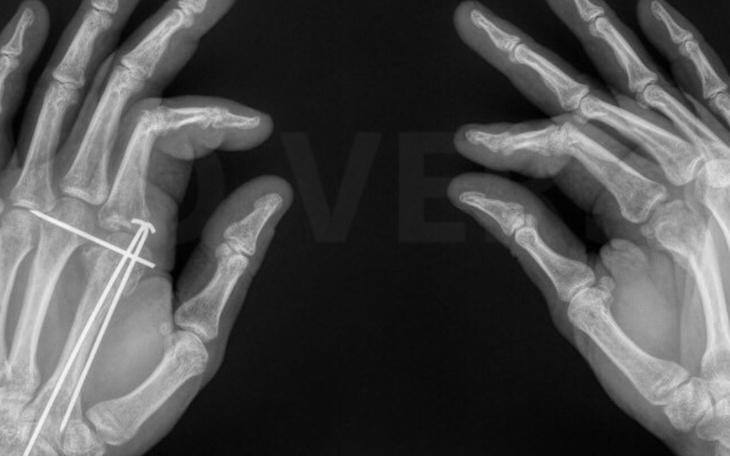

W efekcie doznał obrażeń głowy i poważnych uszkodzeń obu dłoni. Tylko dzięki temu że dał radę się jakoś zasłonić, najbardziej ucierpiały kości dłoni a nie czaszki. Przez długi czas miał unieruchomione obie ręce w gipsie i założone druty umożliwiające zrośnięcie się kości. Przez kilka miesięcy był całkowicie niesamodzielny i proste czynności takie jak jedzenie wymagały pomocy i sprawiały ogromny ból.

Po wykonaniu serii kosztownych badań, dowiedzieliśmy się konieczna będzie kolejna operacja a z opinii lekarskiej wynika, że nierówności kostne spowodowane dosłownie strzaskaniem stawów twardym narzędziem przez napastnika będą blokowały ruch, powodowały zwyrodnienie stawu i z czasem sprawiały coraz większy ból...